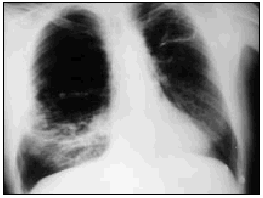

Varón de 60 años, diabético y con insuficiencia respiratoria crónica por enfisema pulmonar que ingresa por una neumonía en el lóbulo medio derecho. Se inició tratamiento con broncodilatadores inhalados, una cefalosporina de tercera generación y un macrólido, con mejoría inicial. En la tercera semana, ante la persistencia de cuadro febril, se realizó una radiografía de tórax (fig. 1) en la que se observa un infiltrado en el pulmón derecho de gran tamaño y con nivel hidroaéreo, por lo que se le añadió un antibiótico anaerobicida. En una TC torácica se observaba la lesión ya conocida (fig. 2. flecha izquierda) y otra pequeña imagen redondeada, con nivel hidroaéreo en su interior, en el espacio prevascular (fig. 2. flecha derecha). El fluido contenido en la lesión mayor era más denso que el agua y tenía burbujas de gas en su interior (fig. 2 punta de flecha). En un cultivo de esputo se cultivó Pseudomonas aeruginosa multisensible. Tras un acceso de tos, en una nueva radiografía de tórax (fig. 3) desaparece el infiltrado derecho, diseminándose la infección pulmonar, falleciendo el paciente días después en situación de shock séptico. Se estableció el siguiente diagnóstico: bullas pulmonares infectadas; bronconeumonía bilateral por P. aeruginosa.

Fig. 1.